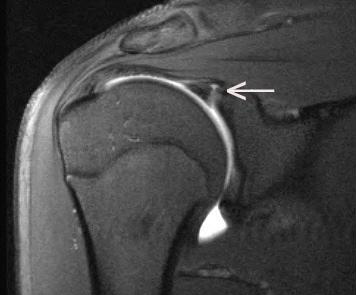

“SLAP tears (a SLAP tear is an injury to the shoulder labrum) are one of the most feared injuries in an overhead throwing athlete like a ballplayer,” Dr. Ciccotti states. “They are a challenge to diagnose and surgery is difficult and not always successful. Research at the Rothman Orthopaedic Institute has focused on improved diagnosis, non-operative treatment and operative treatment of SLAP tears.  Injuries like SLAP tears are the reason we take such an academic approach at the Rothman Orthopaedic Institute. We are always looking to get better, to push the boundaries of science and find the best evidence-based answers for our patients. I hope that one day our research into injuries like SLAP tears produces results that make this injury far easier to diagnose and treat. Maybe one day this injury won’t be one of the most difficult we see? But then it will be something else and we will go to work on that. That’s the kind of work I find very exciting in both my roles here with the Phillies and with the Rothman Orthopaedic Institute.”